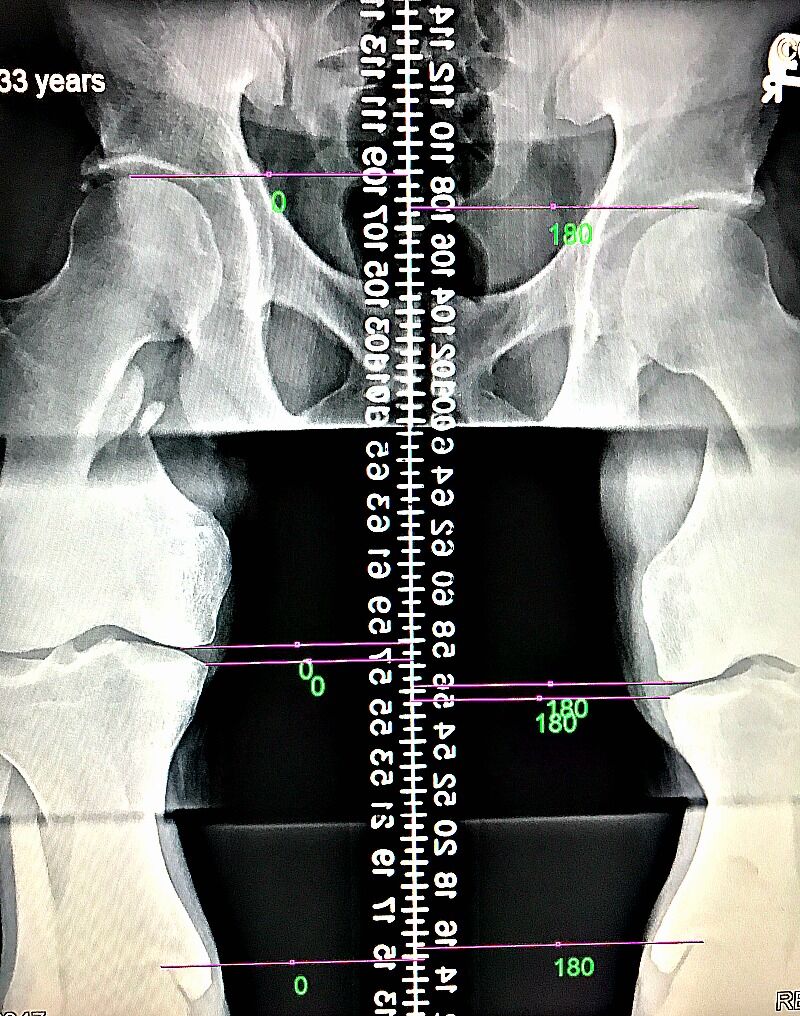

LLD may affect 60 – 90% of people, which is why it should be evaluated and considered a factor in patients seeking chiropractic care. Measurement by x-ray is the most accurate measurement method and since we’re looking at millimeters of difference, it is what we recommend.

After a physical examination, we will determine if x-rays are necessary. If we end up taking x-rays of the lumbar spine and pelvis, we will take measurements of the height of the femur heads to look for a measured difference. If a leg length difference greater than 3mm is present on x-ray, we will make note that the patient is a good candidate for a leg length discrepancy x-ray.